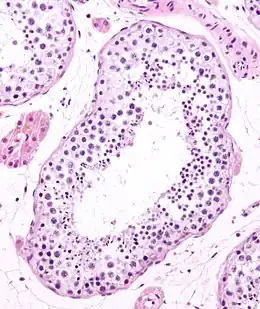

Les tubes séminifères (du latin : semen-ferre : « qui porte la semence ») sont le siège de la formation des spermatozoïdes (spermatogenèse) dans les testicules. Chaque testicule est composé de 200 à 300 lobules testiculaires séparés par une cloison conjonctive et chaque lobule comprend 1 à 4 tubes séminifères, il y a donc environ 500 tubes séminifères par testicule.

Les tubes séminifères font entre 30 et 80 cm de long pour 150 à 250 μm de diamètre. Ils sont entourés d'un tissu conjonctif contenant des cellules de Leydig sécrétant la testostérone.

Deux types de cellules forment l’épithélium des tubes séminifères [1]:

- les cellules de Sertoli grandes et coniques, ne se répliquent pas après la puberté. Entre les membranes latérales de ces cellules se créent des jonctions serrées entre lesquelles se dégagent de petits espaces formant un réseau ;

- dans ces espaces, se trouvent les cellules germinales.

La paroi des tubes se nomme « gaine péritubulaire » elle est constituée d'une lame basale et de collagène (en grand nombre). Celle-ci est limitée par la matrice extracellulaire. La gaine a une épaisseur de 5 micromètres.

La multiplication des cellules souches se fait à la périphérie des tubes séminifères. En remontant vers la lumière du tube séminifère, les cellules filles mûrissent progressivement et se transforment en spermatozoïdes une fois arrivées dans la lumière.